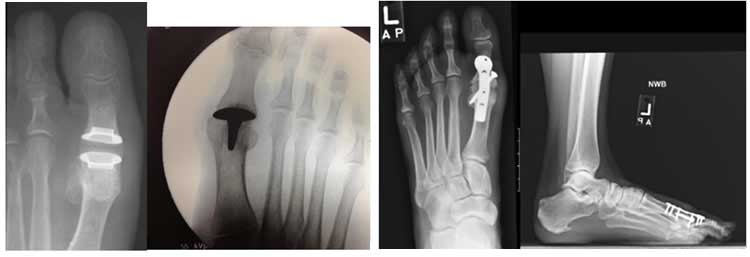

Dr. Devon一并介紹了另外兩種備選術(shù)式: “Waterman 截骨切開(kāi)術(shù)/微型自體骨軟骨移植修復(fù)術(shù)”和“跖趾關(guān)節(jié)移植/融合術(shù)”(下圖示)。